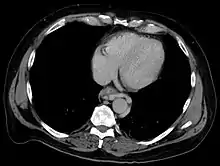

![]() | |

| Gastroscopy image of esophageal varices with prominent cherry-red spots and wale signs | |